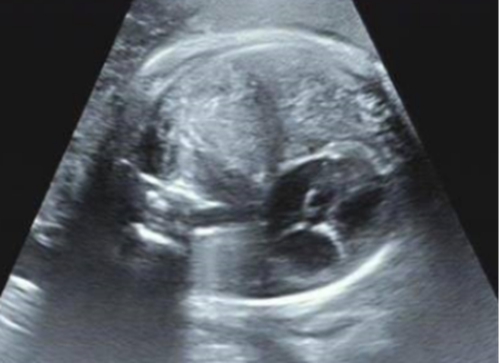

被告知檢查結果后,胡女士一家開始四處求醫(yī),經(jīng)多方打聽,他們來到青島婦女兒童醫(yī)院尋求解決辦法。胎兒醫(yī)學中心接診專家為胡女士完善排畸超聲相關檢查后,診斷胎兒患有先天性膈疝。

先天性膈疝是一種是宮內(nèi)少見的出生缺陷,產(chǎn)前發(fā)生率約為1/10000。嚴重的先天性膈疝可導致肺發(fā)育不良和肺動脈高壓。

“人體內(nèi)胸腔、腹腔由一層叫做膈肌的肌肉分離開,由于胎兒的膈肌缺損,現(xiàn)在腸管通過膈肌的孔洞,’竄’入胸腔,把原本應該在左側胸腔的心臟擠到了右側胸腔......”聽著專家的解釋,胡女士夫妻倆的心一下子懸了起來?!昂⒆右呀?jīng)在肚子里8個月了,情況到底怎么樣?”

為綜合評估胎兒的情況,產(chǎn)科中心、胎兒醫(yī)學中心、超聲科、小兒外科、心臟中心及麻醉科專家進行多學科會診,專家評估后認為胎兒為晚發(fā)型膈疝,評估肺頭比LHR2.8,觀測/臍帶LHR>55%,出生后生存率接近100%。好消息令夫妻倆喜極而泣。